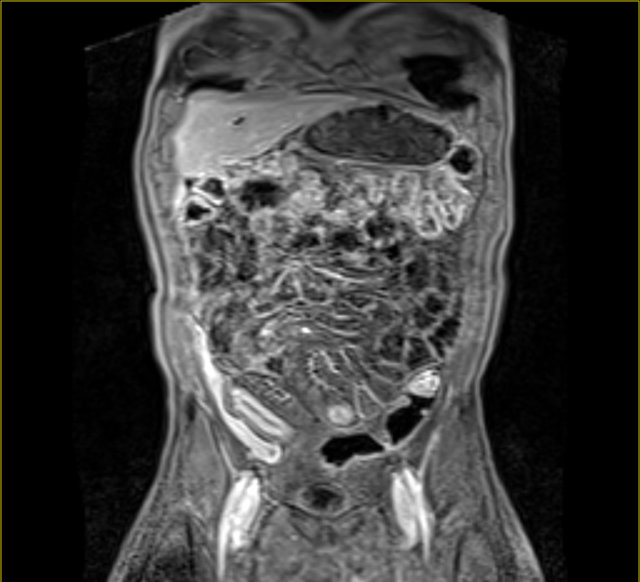

Resonancia Magnética Enfermedad Inflamatoria Intestinal, , , , , , , 0, EPOS™ - S-0978, epos.myesr.org, 1224 x 1863, jpeg, WebLa enfermedad inflamatoria intestinal (EII) comprende principalmente la colitis ulcerosa crónica idiopática (CUCI) o colitis ulcerosa, la enfermedad de Crohn (EC) y la colitis. WebLa resonancia magnética (RM) es una técnica de imagen que no utiliza radiación ionizante y permite identificar cambios inflamatorios en el intestino delgado y el colon, así como., 20, resonancia-magnetica-enfermedad-inflamatoria-intestinal, Novedades y Muebles WebLa enfermedad inflamatoria intestinal (EII) comprende principalmente la colitis ulcerosa crónica idiopática (CUCI) o colitis ulcerosa, la enfermedad de Crohn (EC) y la colitis. WebLa resonancia magnética (RM) es una técnica de imagen que no utiliza radiación ionizante y permite identificar cambios inflamatorios en el intestino delgado y el colon, así como.

WebLa enterografía por resonancia magnética (RM) es un estudio por imágenes que produce fotografías detalladas de su intestino delgado. Podría ayudar a su médico a diagnosticar. WebLa enfermedad inflamatoria intestinal es una patología crónica secundaria a una respuesta inmune no controlada en la mucosa gastrointestinal, con manifestaciones inespecíficas.

WebEl objetivo de investigación de la Unidad de Enfermedad Inflamatoria Intestinal del Hospital Clínic de Barcelona es desarrollar una investigación traslacional que resulte en una. WebEl objetivo de la ENTERO – RM, también llamada RESONANCIA DE INTESTINO es visualizar las paredes del intestino, y poder determinar si presenta alguna. WebResonancia Magnética en el diagnóstico de las enfermedades intestinales. La Resonancia de Intestino también se llama Entero Resonancia y es una prueba. WebLa investigación de la EII se realiza a través del grupo de Enfermedad Inflamatoria Intestinal del IDIBAPS, dentro del Área de Hígado, Sistema digestivo y metabolismo. Las. WebEl objetivo del tratamiento de la enfermedad intestinal inflamatoria es reducir la inflamación que desencadena los signos y síntomas. En el mejor de los casos, podría. WebLos tipos de enfermedad inflamatoria intestinal incluyen: Colitis ulcerosa : esta condición causa una inflamación duradera y úlceras en el revestimiento del.